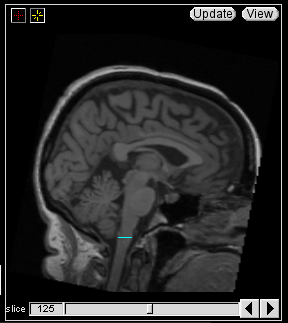

In the Sagittal view, locate the Obex on the Brainstem. Select the 'ignored contour' (e.g. the cyan color) and draw a horizontal line from this point to the anterior most part on the brainstem.

This line will appear as a cyan dot in the Coronal view and mark the inferior boundary of the brainstem.